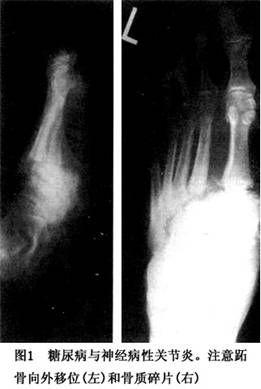

相关图片